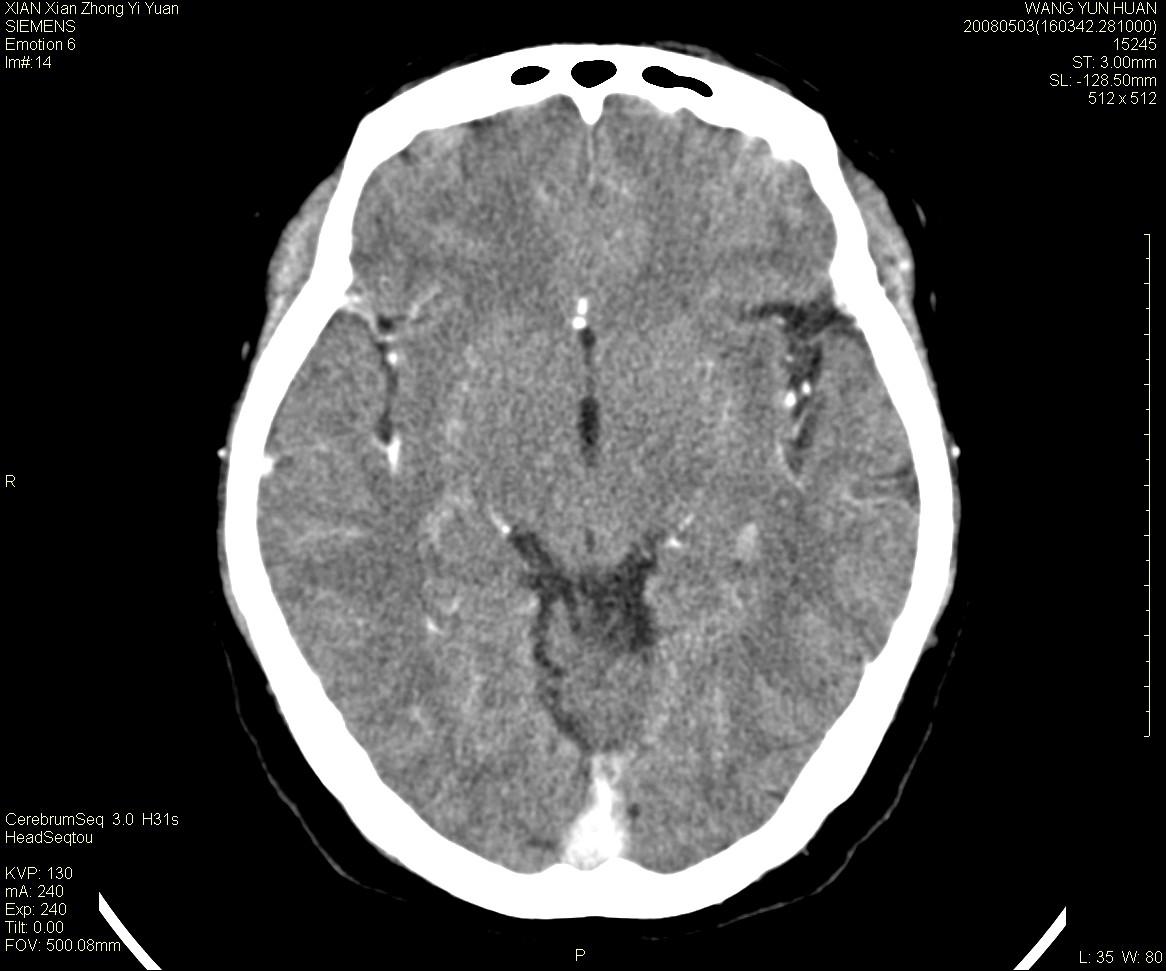

病灶显示轻度强化,ct增加4hu左右,大家看是什么肿瘤.

强化后动脉期及延迟2分钟,五分钟图像

小脑蚓部囊型肿块,内有实性结节及钙化点。增强后囊壁及结节轻度强化。

考虑蚓部星形细胞瘤(ⅱ级可能性大)。

小脑蚓部肿块,周围无明显占位效应及水肿带,增强轻度强化,考虑低分级星形细胞瘤。